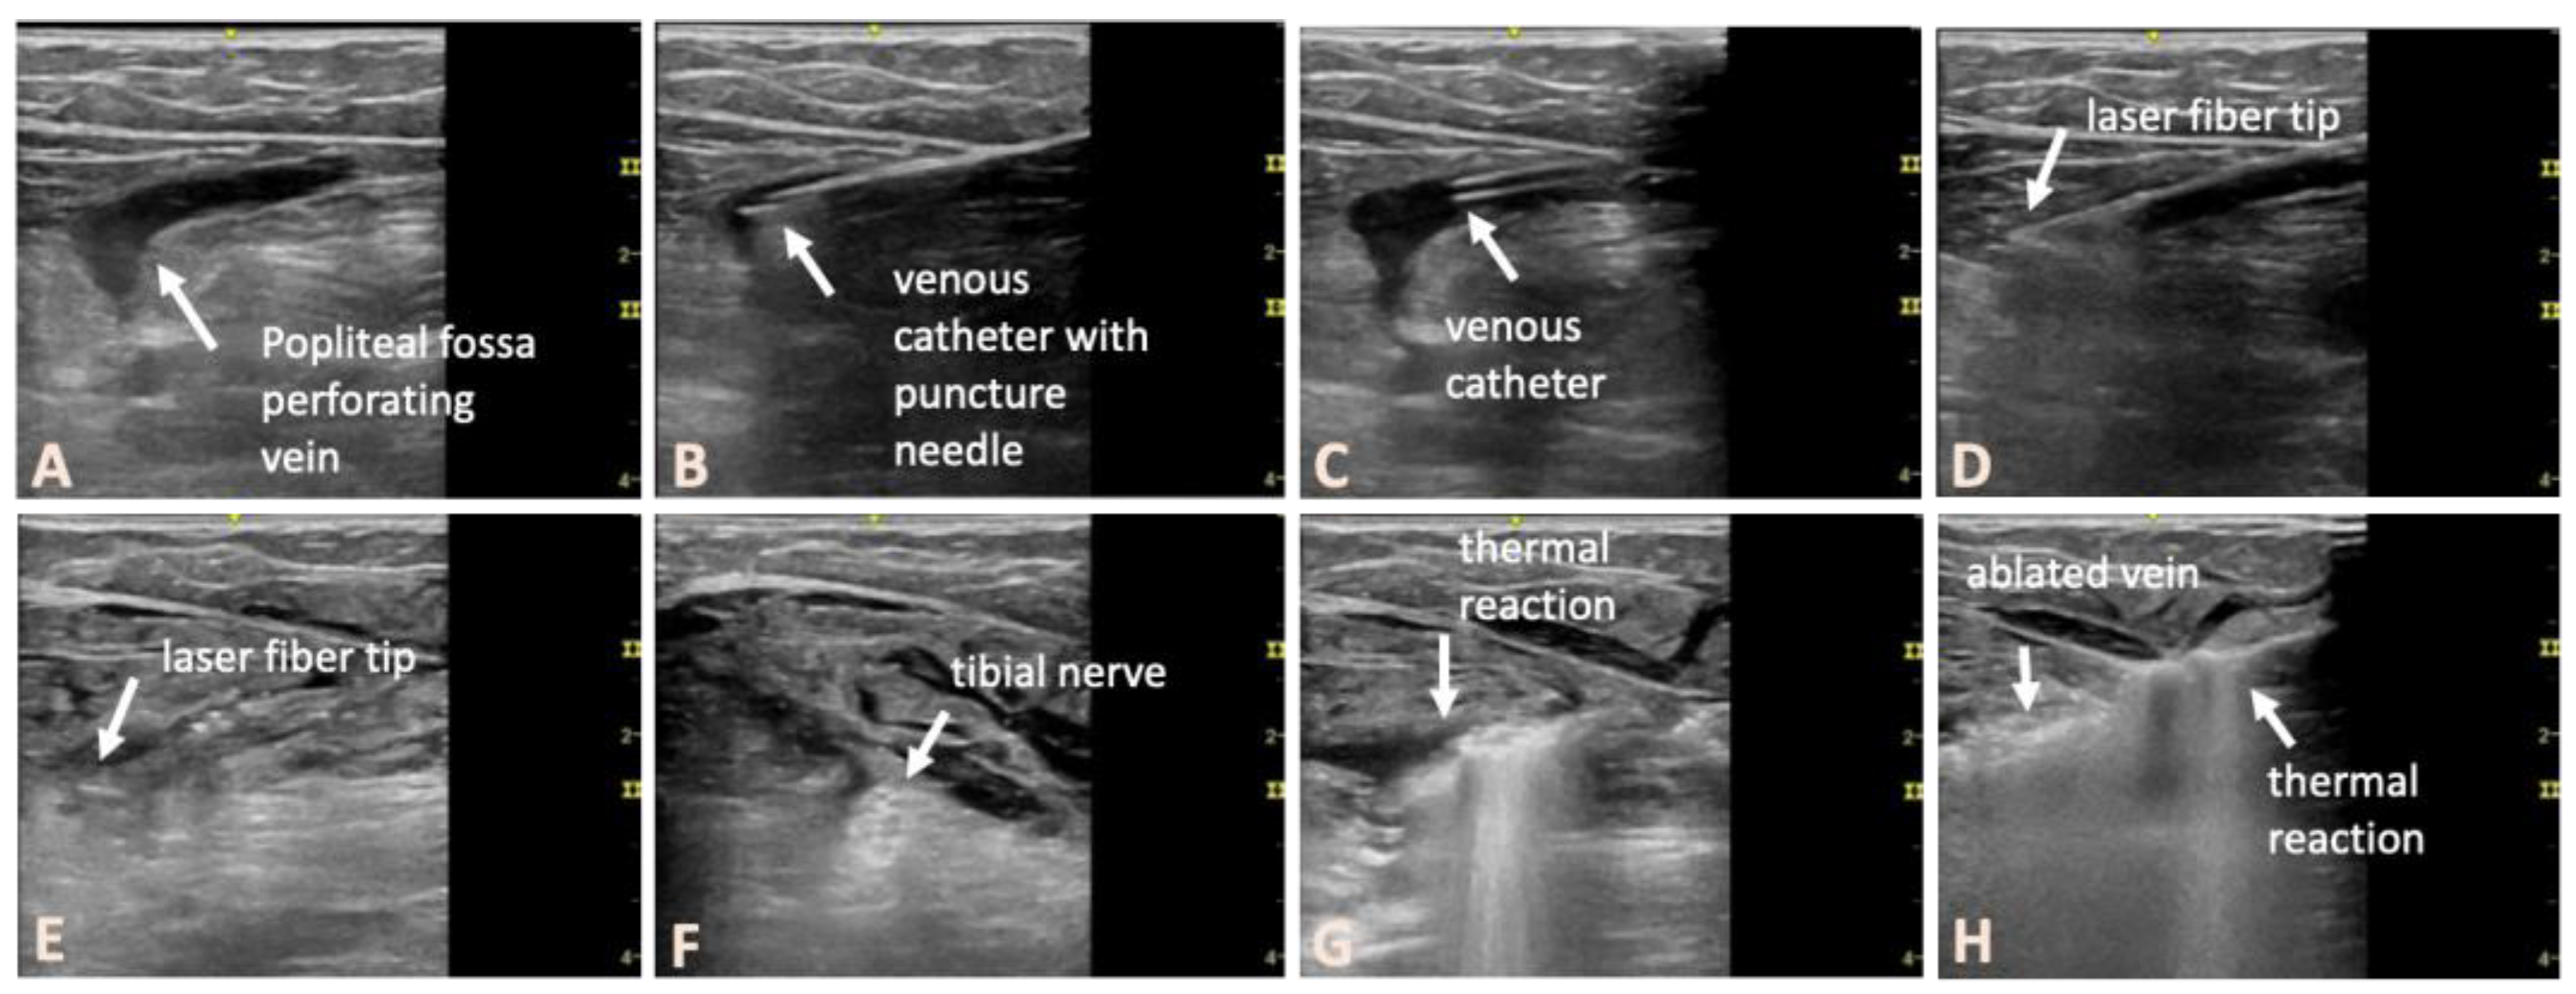

2.3. Interventional Treatment